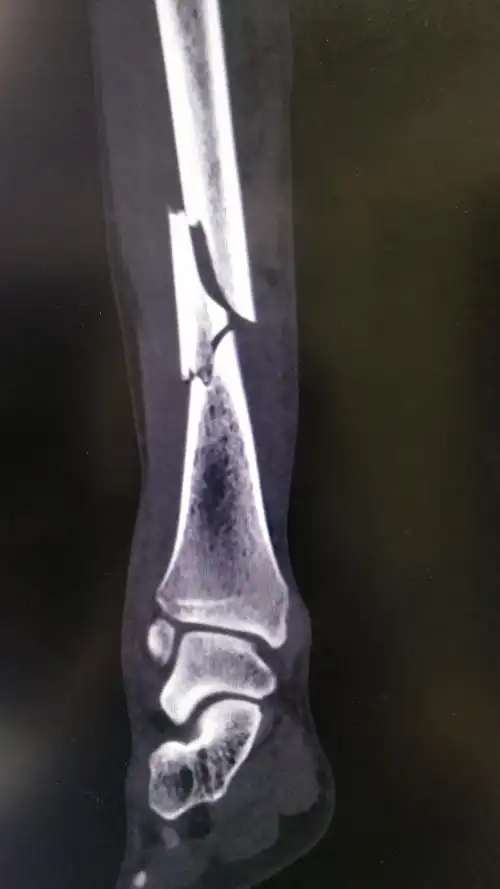

一例严重的胫腓骨远端粉碎骨折